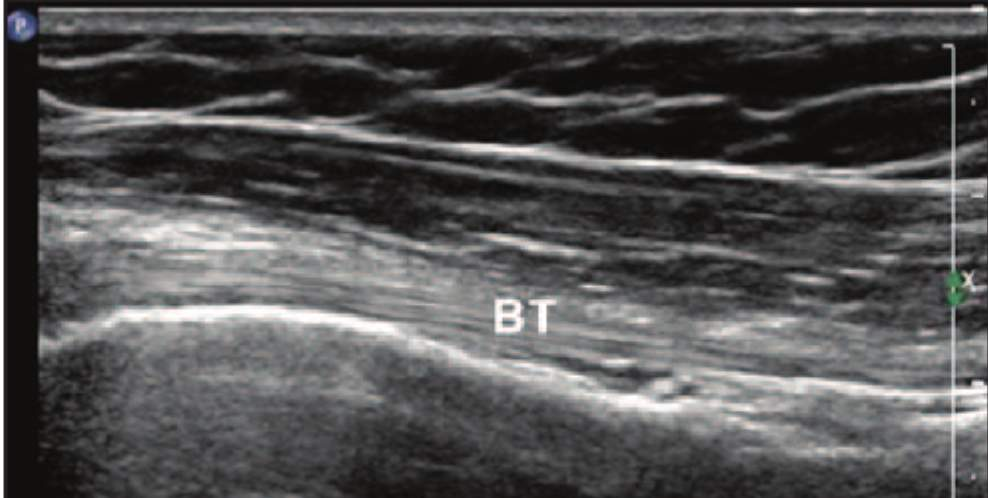

ultrasound: tendon

comprise multiple individual, longitudinally oriented, parallel collagen fibers that are tightly bundled, resulting in a fibrillary pattern on ultrasound

This results in the characteristic hyperechoic appearance of tendons when the US beam is oriented 90 degrees to the tendon